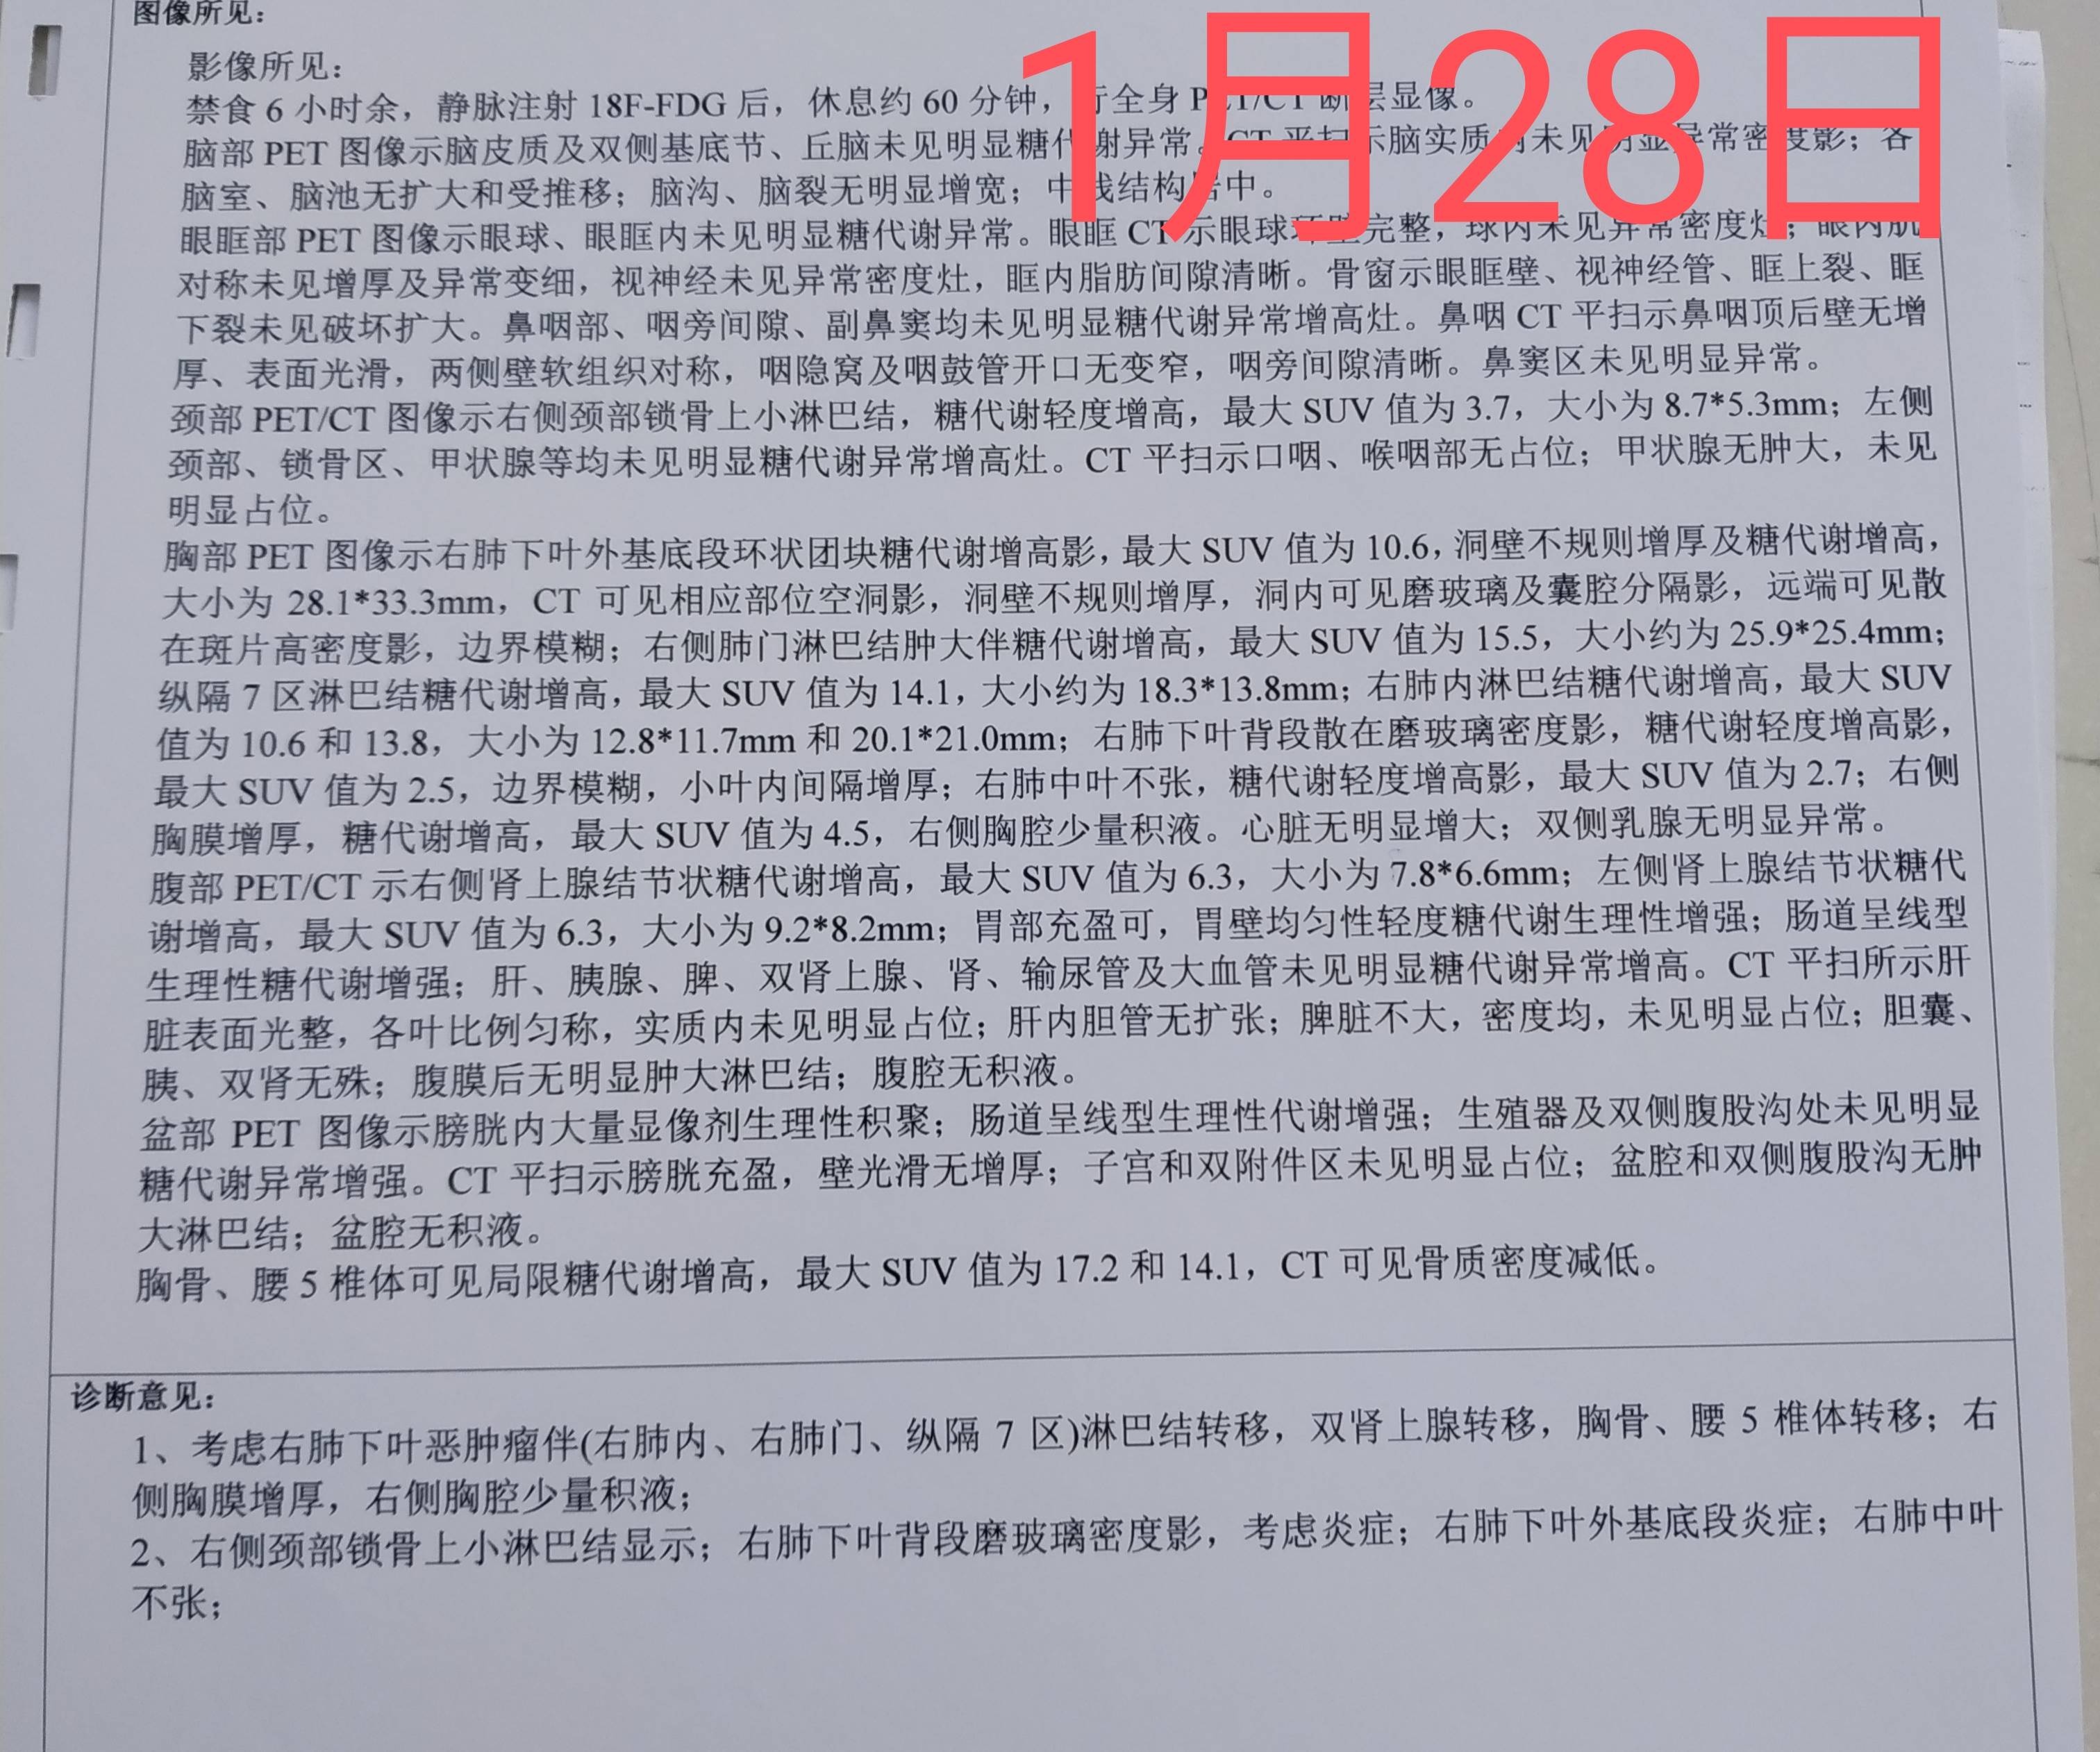

25号下午做的ct,当天晚上我就在手机上看到了报告,没写大小,感觉不妙,心里非常慌。

今天早上让爸爸取完ct就发给我,真的是没有好转。

下周一穿刺取病理,看看有可能是小细胞吗?